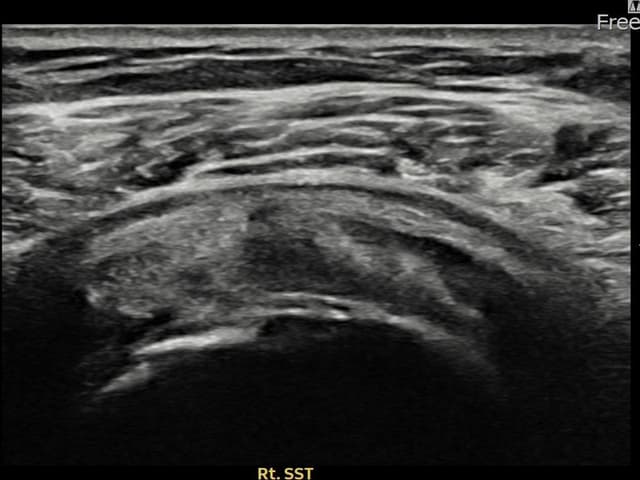

[촬영시기:23.07.31~23.09.27]

[어깨인대 축소봉합술] 좌측 어깨 극상근건 광범위 파열로 수개월간 일상생활이 어렵던 중 내원하셨습니다.